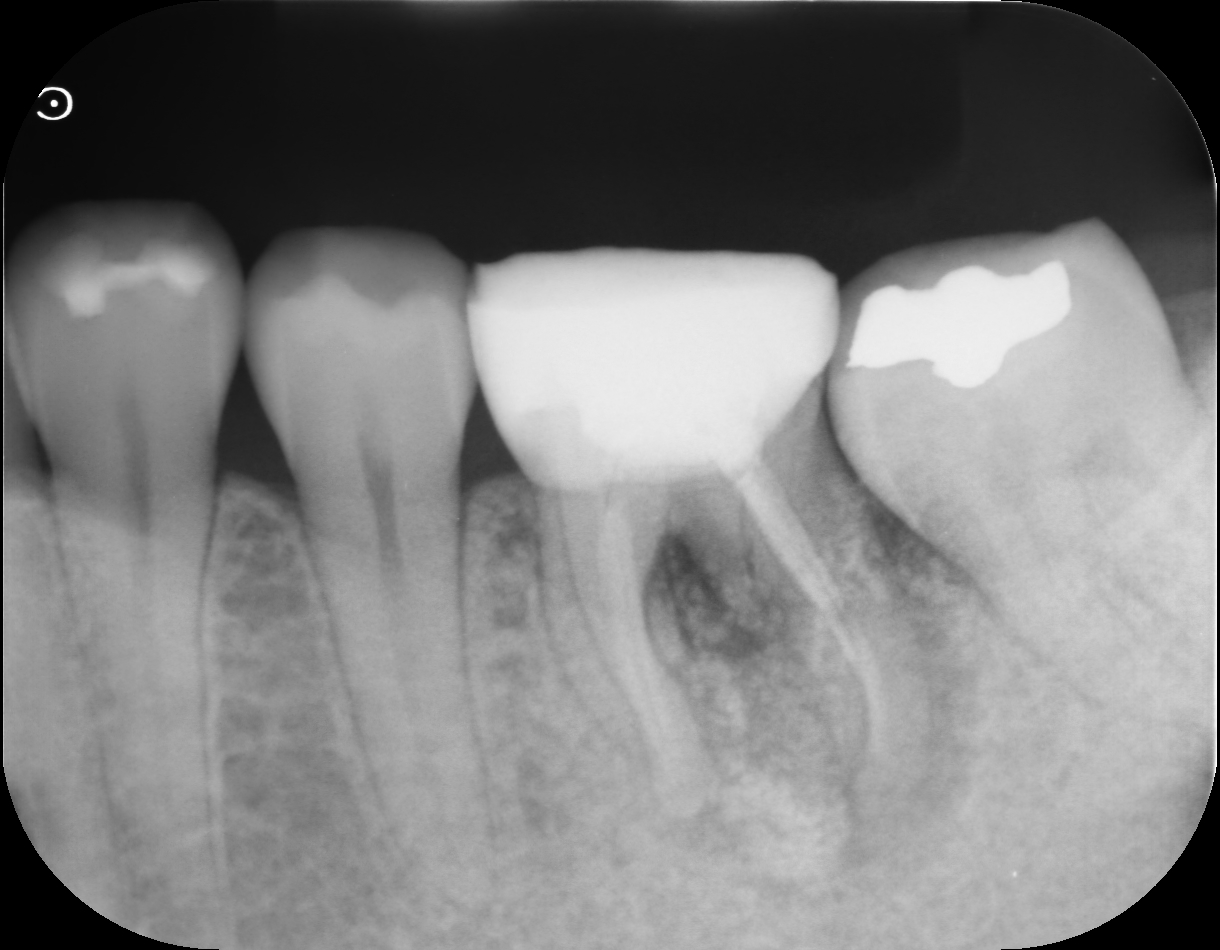

before

左下第一大臼歯の歯が割れてしまい、歯を残すことができない状態だったため、抜歯を行いました。

割れた歯をそのままにしておくと、痛みや腫れ、感染の原因になるため、適切なタイミングでの処置となりました。

| 主訴 | 左下6番の歯が割れた |

| 診断名/主な症状 | 左下第一大臼歯歯根破折 |

| 治療内容 | 抜歯、骨造成術、インプラント即時埋入術 |

| 抜歯部位 | 左下第一大臼歯 |